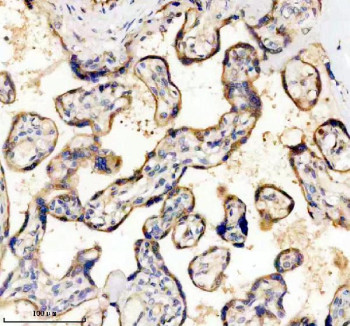

Antibody in PBS with 0.02% sodium azide, 50% glycerol and 0.4-0.5mg/ml BSA. CD39 antibody is a widely used reagent for studying immune regulation, purinergic signaling, and vascular biology. The encoded protein, CD39 (also known as ectonucleoside triphosphate diphosphohydrolase 1 or ENTPD1), is an ectoenzyme expressed on the surface of endothelial cells, immune cells, and platelets. CD39 hydrolyzes extracellular ATP and ADP into AMP, which can then be converted into adenosine by CD73. This ATP-adenosine pathway regulates inflammation, thrombosis, and tissue homeostasis by balancing proinflammatory and immunosuppressive signals.In the immune system, CD39 plays an important role in controlling T cell and regulatory T cell activity. By reducing extracellular ATP levels and increasing adenosine production, CD39 dampens inflammatory responses and promotes immune tolerance. High CD39 expression on regulatory T cells contributes to their immunosuppressive capacity, making CD39 a focus of interest in autoimmune disease, transplantation, and cancer immunology. In the vascular system, CD39 helps prevent platelet aggregation and thrombosis by degrading platelet-activating nucleotides, thereby maintaining vascular health.Dysregulation of CD39 expression or activity has been implicated in diverse diseases. Increased CD39 activity has been observed in tumors, where it contributes to immune evasion by creating an adenosine-rich, immunosuppressive microenvironment. Conversely, reduced CD39 function has been linked to heightened inflammation in autoimmune diseases and transplant rejection. These associations underscore CD39 as both a biomarker and a therapeutic target across multiple areas of biomedical research.At the molecular level, CD39 is a transmembrane glycoprotein with two transmembrane domains and large extracellular loops that contain conserved apyrase motifs responsible for nucleotide hydrolysis. Its enzymatic activity is dependent on divalent cations such as calcium and magnesium. By regulating extracellular nucleotide concentrations, CD39 serves as a critical checkpoint in purinergic signaling pathways that influence vascular tone, immune cell communication, and tissue repair.The CD39 antibody is commonly used in flow cytometry, western blotting, immunohistochemistry, and immunofluorescence to detect protein expression and distribution. These applications are valuable for research in immunology, oncology, and cardiovascular biology. For scientists investigating immune regulation, thrombosis, or purinergic signaling, the CD39 antibody provides a specific and dependable detection tool. NSJ Bioreagents supplies validated antibodies designed to ensure reproducibility and accuracy in advanced molecular studies.

| Application: | WB, IHC (paraffin) |